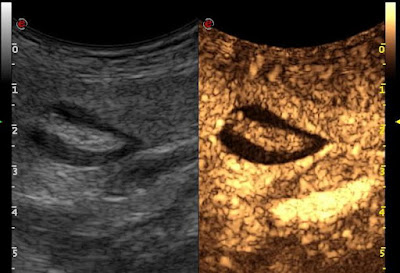

| hasonló megjelenés UH vizsgálattal axialis… |

| …és coronalis síkban |

| kontrasztanyagos UH vizsgálattal látszik, hogy a kérdéses elváltozás vascularisatiot nem mutat |